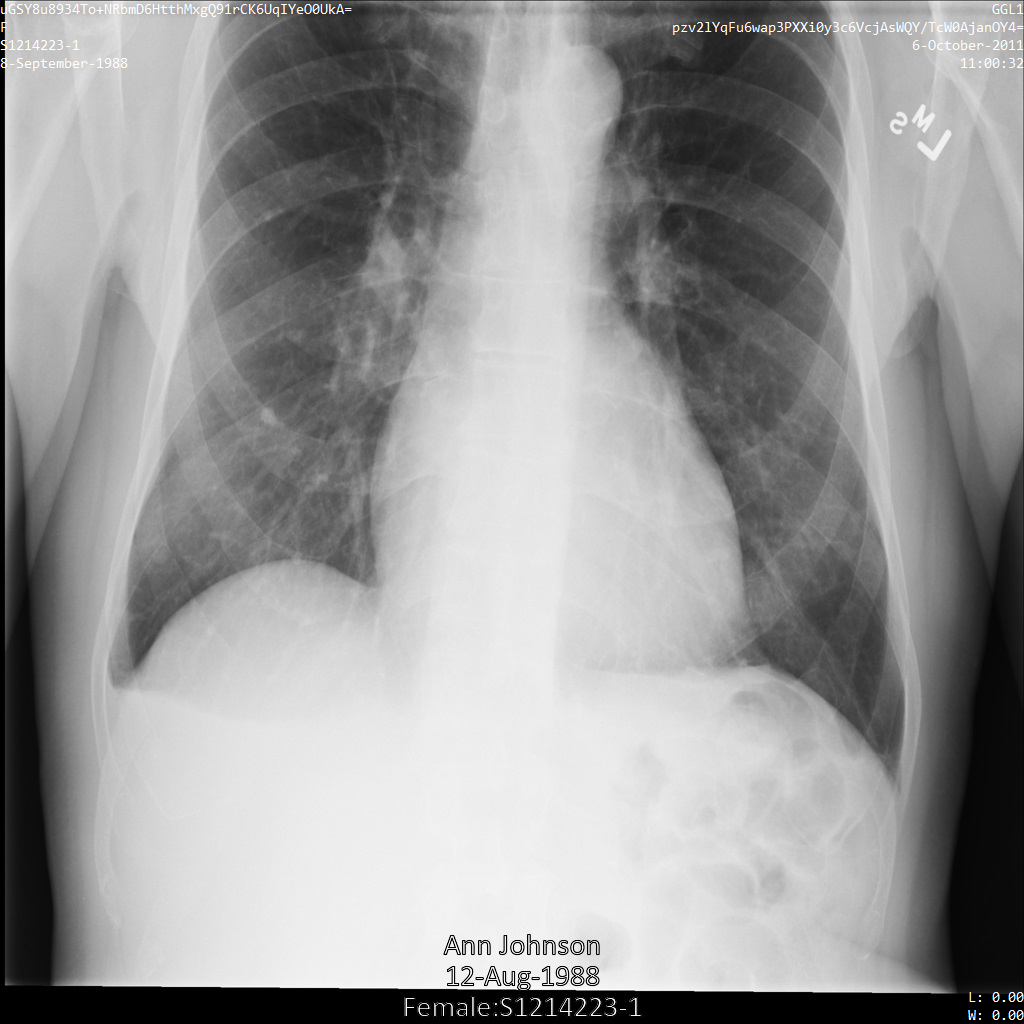

Chacune des sections suivantes fournit des exemples d'anonymisation de données DICOM à l'aide de différentes méthodes. Une sortie de l'image anonymisée est fournie avec chaque échantillon. Chaque exemple utilise l'image d'origine suivante comme entrée :

Vous pouvez comparer l'image de sortie de chaque opération d'anonymisation à cette image d'origine pour voir les effets de l'opération.

Une fois l'image envoyée à l'API Cloud Healthcare, elle apparaît comme suit. Alors que les métadonnées affichées dans les angles supérieurs de l'image ont été masquées, les informations de santé protégées qui sont incluses dans l'angle inférieur de l'image sont conservées. Pour supprimer également le texte incrusté, consultez la section Masquer le texte incrusté dans les images.